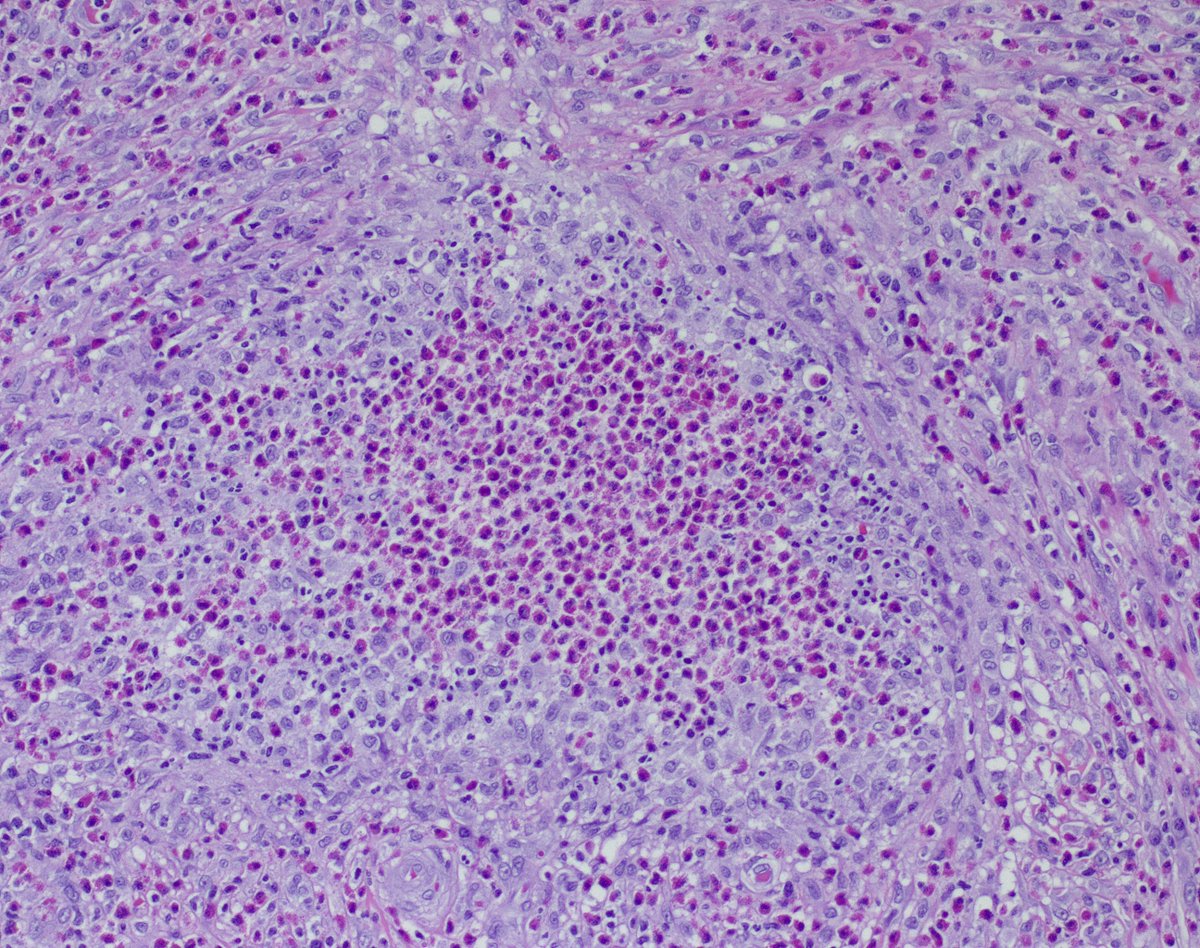

20s♂️ in good health, 4 months hx of 'cyst' axilla. Tons of eos, mostly in the dermis, also focally in the epidermis. Slam dunk persistent/exuberant arthropod 'bite', or something else? What would you include in the ddx? Ty! Tim McCalmont Henry YANG Dermpath_doc_trish Diego Morales, MD Etan Marks, DO

20s♂️ in good health, 4 months hx of 'cyst' axilla.

Tons of eos, mostly in the dermis, also focally in the epidermis.

Slam dunk persistent/exuberant arthropod 'bite', or something else?

What would you include in the ddx? Ty!